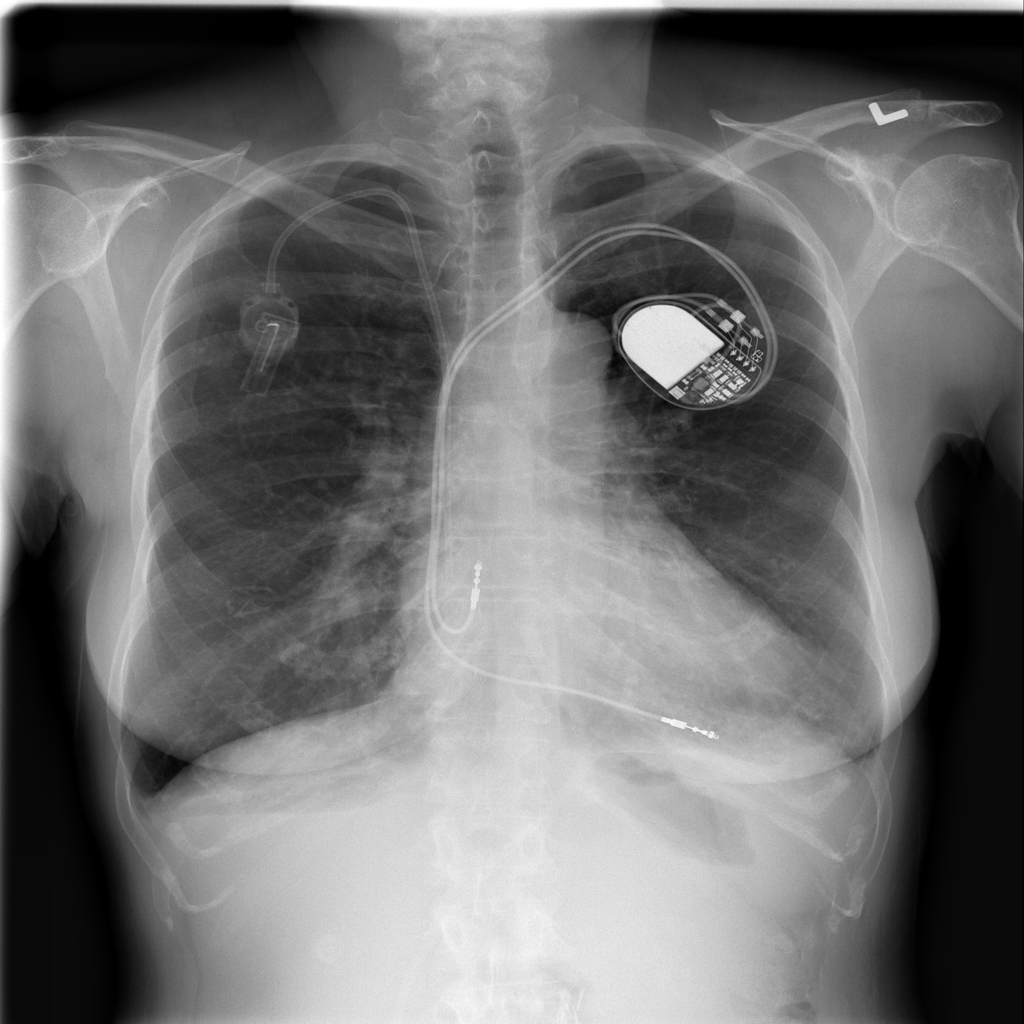

PAT-86C8 · IMG-000Effusion

PAT-86C8 · IMG-000

PA